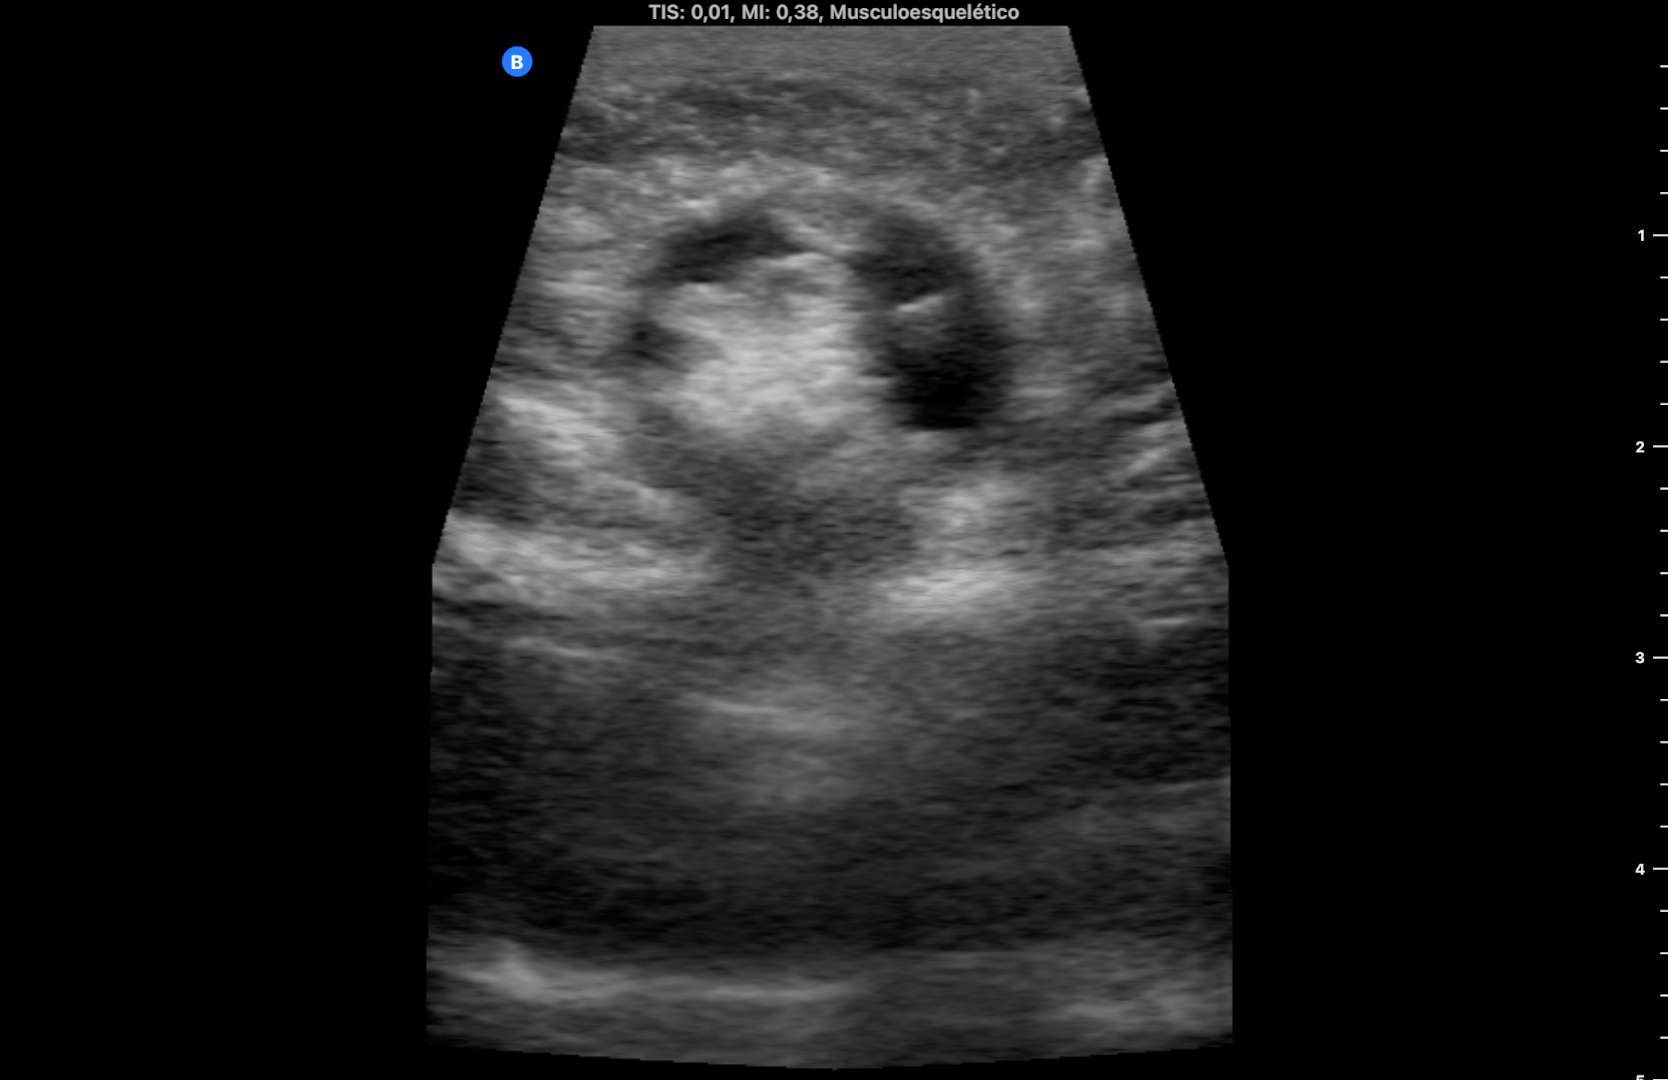

Se utiliza en la misma consulta una sonda portátil con preset de partes blandas, observando una imagen heterogénea redondeada, rodeada de líquido anecogénico a nivel subcutáneo que rompe la línea alba (imagen 1). Durante la exploración se comprime con la sonda en el lugar de la imagen consiguiendo la reducción de la misma y desapareciendo el dolor. La ecografía muestra entonces la discontinuidad de la línea alba con una pequeña protrusión de grasa (imagen 2) (se dispone de vídeos).

Hernia umbilical incarcerada reducida en el momento de la consulta. El diagnóstico diferencial debe hacerse con lipomas, hernias epigástricas, diástasis de rectos, onfalitis supurativas o metástasis umbilicales de carcinomas intraabdominales denominadas «nódulo de la hermana María José».

La ecografía en el ámbito de la Atención Primaria permite el diagnóstico (y a veces el tratamiento) en determinadas situaciones clínicas. Aunque el diagnóstico de hernia umbilical es clínico, la ecografía permite detectar los signos de sufrimiento (líquido periherniario) que indican la necesidad de reducción inmediata, y si no se consigue, derivación urgente al hospital.